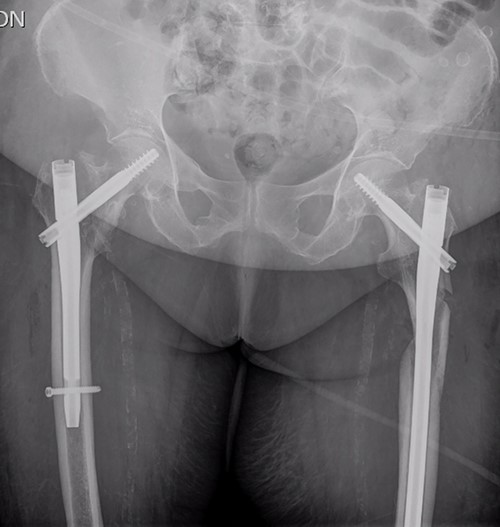

On examination, external rotation deformity of both lower limbs was evident, as well as pain upon palpation in the trochanteric region and during mobilization. The radiological study revealed a left and a right intertrochanteric femur fracture (Fig. 1). She was given analgesia, immobilized with two cutaneous tractions (Fig. 2), and was admitted to the Orthogeriatric Unit.

A. Anteroposterior pelvis radiograph evidencing a left subtrochanteric (AO:32-B2a) and a right intertrochanteric femur fracture (AO:31-A2.3). B. Radiograph of the right hip without any criteria of fracture instability. C. Radiograph of the left hip showing a simple wedge pattern of fracture.